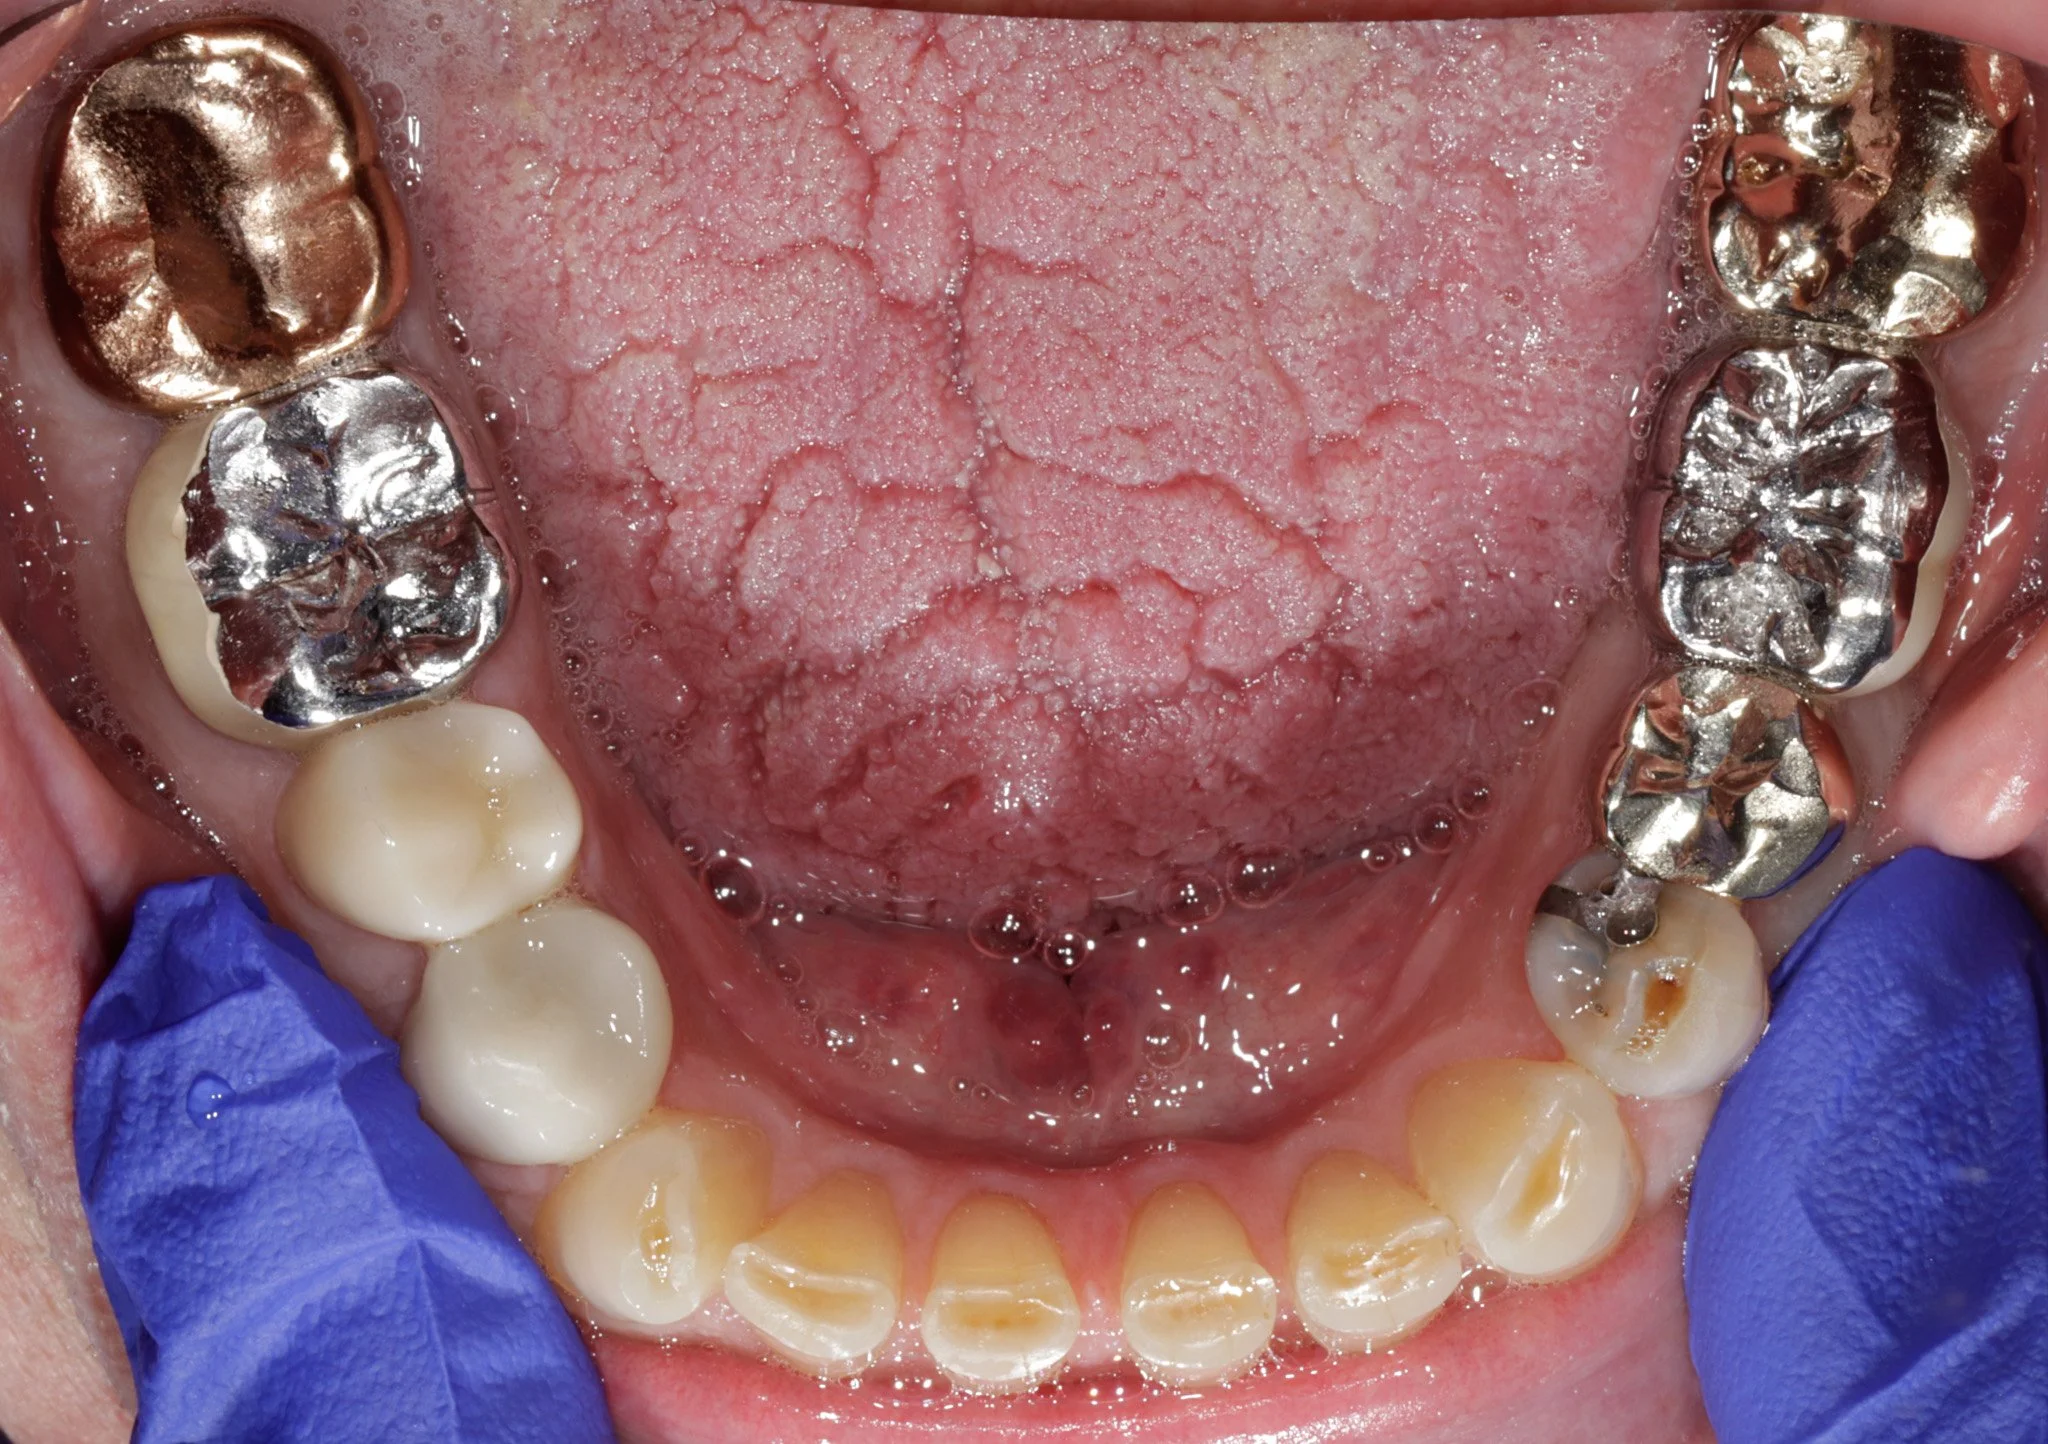

A patient's teeth with old, failing dentistry. Prior to restoring.

Before: Old dentistry that doesn’t fit, decay, acid erosion